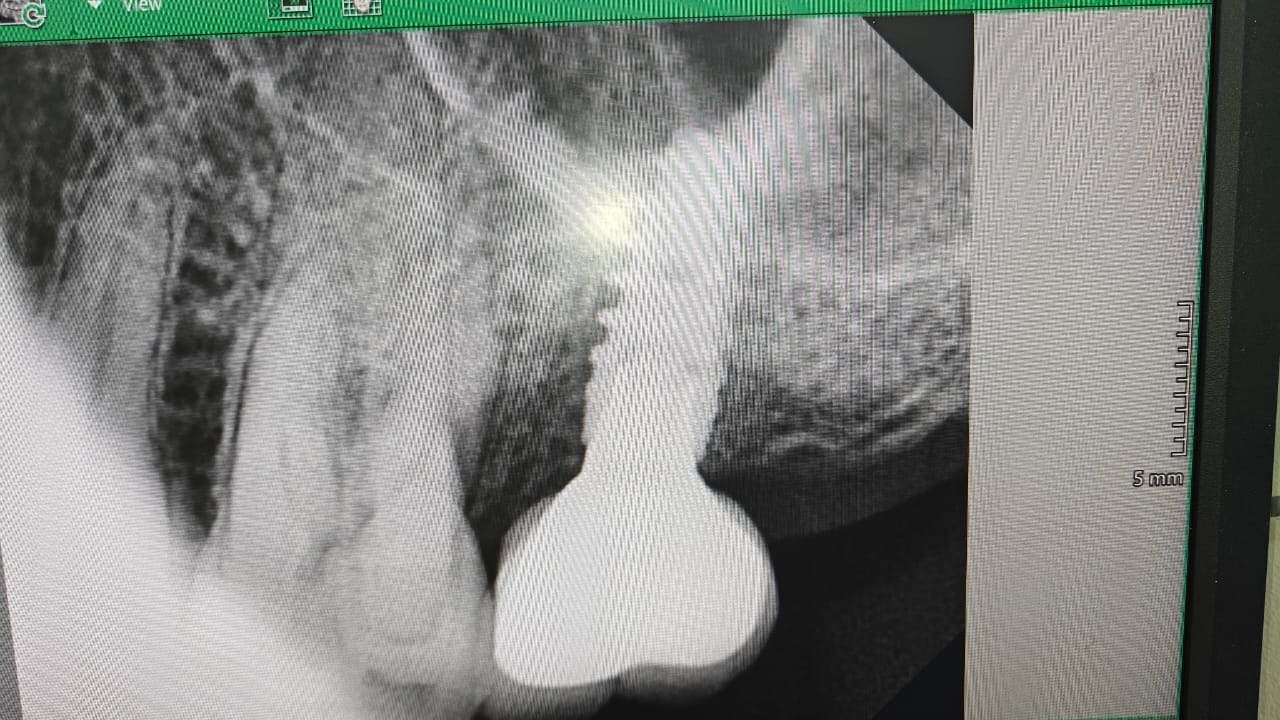

Now final prosthesis that is crown delivered to the patient

Immediate extraction and implant placement with 27.